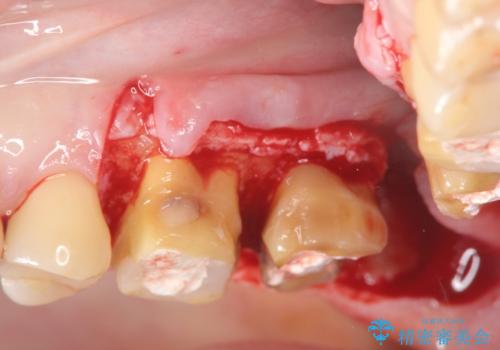

・深い虫歯 →歯周外科を行うことで歯ぐきの腫れを改善

・根尖性歯周炎 →精密根管治療